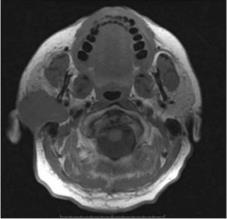

Mágneses rezonancia (Magnetic Resonance Imaging, MRI)

A számítógépes rétegvizsgálatot nem helyettesítő, hanem azt jólkiegészítő eljárás, mely elsősorban a nyálmirigyek tumoros elváltozásainak differenciáldiagnosztikájában alkalmazható módszer (12.5. ábra). Különösen jó hatásfokkal alkalmazták pleomorph adenomák recidívája esetén a kiújuló tumorok számának és kiterjedésének megítélésére (12.6. ábra). A módszer, ionizáló sugárzás alkalmazása nélkül képes nagy felbontású tomográfiás felvételek készítésére bizonyos szervekről, beleértve a nyálmirigyeket is. A módszer lényegében a különböző szövetek víztartalmáról nyújt alapvető információkat. Képes az ép és a kóros szövetek közti minimális különbség kimutatására is. A módszer hátránya időigényessége, kontraindikált volt pacemakerimplantáció, illetve intraoralis fémtárgyak (pl. rögzített fogpótlás, fix fogszabályozó készülék) esetében.

12.6. ábra. Jobb oldali parotis tumor MRI felvétele(Dr. Kollár József anyagából)